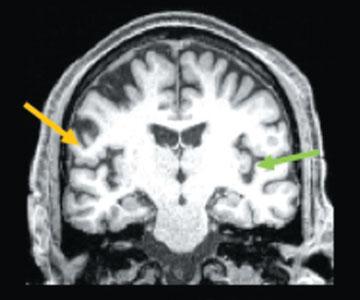

Obesity's Lasting Effect on Brain Signals

Donovan Garner

Biology

Medicine

Anatomy

From The Staff